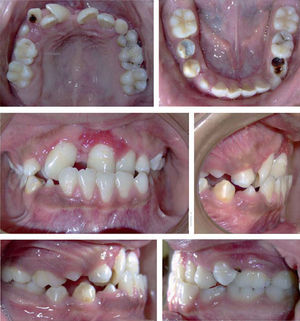

Análisis facial. El paciente presenta un patrón leptoprosopo, con una asimetría facial y surcos nasolabial y subnasal marcados debido a la depresión de la porción superior del tercio inferior. Su perfil es convexo con un mentón poco prominente; un labio superior retraído y el labio inferior protruido en relación con la línea estética.

Análisis intraoral. La línea media dental inferior está desviada a la izquierda. Se observa una mordida cruzada anterior y en relación céntrica el contacto entre incisivos no llega a ser borde a borde. En oclusión céntrica se obtiene una sobremordida horizontal negativa de -2mm con una relación molar clase I. La dentición es mixta con caries, presentaba restauración de amalgama en el 45 y caries en los órganos dentarios 53, 55, 24, 65, 74 y 75.

El labio superior, en relación con la línea estética, se encontraba en una posición retruida y el labio inferior en protrusión. El ángulo nasolabial estaba aumentado por el poco soporte labial que ofrecían los centrales superiores (Figuras 1 a 5).

DentalRelación molar clase I, incisivos superiores retroclinados, incisivos inferiores en norma, dentición mixta, mordida cruzada anterior, forma de arcos superior e inferior cuadrados, sobremordida horizontal de -2mm y sobremordida vertical de 3.5mm.

FacialLeptoprosopo, asimetría facial, surcos nasolabial y subnasal acentuados, depresión de la porción superior del tercio inferior, perfil convexo, mentón poco prominente, labio superior retraído e inferior protruido.